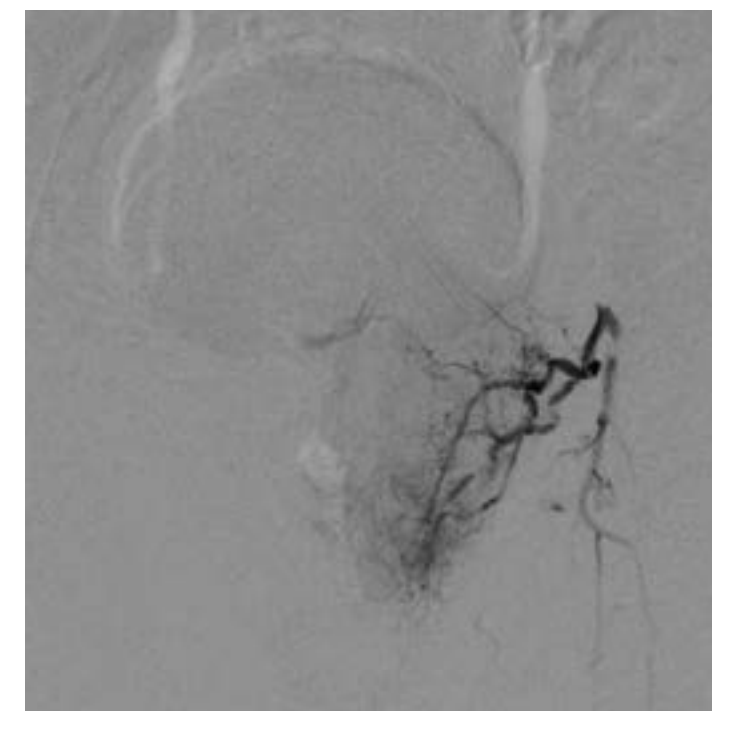

A 74-year-old male with past medical history of hypertension, coronary artery disease, and BPH with LUTS refractory to medical management presented for evaluation. The patient underwent an MRI of the prostate demonstrating a 182 cc gland with an enlarged transitional zone measuring 144 cc (Figure 1). The patient’s baseline IPSS and QoL were 18 and 5, respectively. Given the patient’s prostate gland size, and medical comorbidities, he elected to undergo PAE for management of his LUTS. On the day of his PAE, right common femoral arterial access was obtained and a pigtail DSA was obtained delineating pelvic arterial anatomy. On the right, the prostatic artery arose from a vesiculoprostatic trunk, with a shared origin with the superior vesicular artery (Figure 2). This was selectively catheterized with a progreat alpha microcatheter (Terumo, Tokyo, Japan), and 016” fathom microwire (Boston Scientific, Marlborough, MA). Angiography demonstrated perfusion of the entire right portion of the gland, without evidence of extra-prostatic supply (Figure 3). Embolization was performed with 300-500 micron Embospheres (Merit Medical, South Jordan, UT) to stasis. On the left, the prostatic artery arose from the left obturator artery (Figure 4). This was subsequently catheterized with the same catheter/wire combination, with angiography demonstrating left glandular perfusion without extra-prostatic supply (Figure 5). Embolization was again performed to stasis with 300-500 micron Embospheres. The patient did well post-procedurally with self-limited urinary frequency and dysuria for 3 days. By 3 months post PAE, the patient reported a significant improvement in his LUTS, with an IPSS/QoL of 3 and 0, respectively.